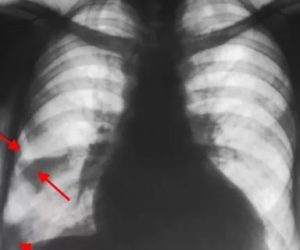

На УЗДГ вен нижних конечностей при инфаркте легкого диагностируется тромбоз глубоких вен. На рентгене легких в боковой и прямой проекциях просматриваются:

• деформация и расширение корня легкого;

• зона снижения прозрачности, имеющая вид клина;

• выпот в плевральной полости.